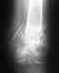

снимок 25.08.11, после которого мне сказали, что нужно полностью гипсовать руку на 2 месяца!

Напомню, до этого стоял аппарат с февраля. Боюсь, что руку уже никогда не разработаю. Кисть не крутится, ну пока и не пытаюсь.

• Кликните для загрузки файла 13. стержень 25.08.11.jpg